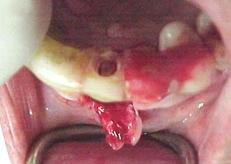

Fotografia 1.5, podemos observar, o enxerto ósseo parafusado em posição. É importantíssimo que o enxerto fique firmemente preso ao osso subjacente.

Fotografia 1.6. Nesta observamos que nos espaços remanescentes, foi colocado uma pasta de material aloplástico, composto por: osso liofilizado, HA e colagel.

Fotografia 1.7. Mostra o enxerto todo recoberto por uma membrana colágena reabsorvível.

Fotografia 1.8. Observa-se que os retalhos foram rigorosamente suturados, contudo, tomando-se cuidado para que não houvesse isquemia nos tecidos, que poderia levar a uma necrose do retalho.

Colocação dos implantes 7 meses após.

Fotografia 1.9. Pode-se ver a perfeita formação do tecido ósseo em toda a área do enxerto, os parafusos de fixação foram removidos.